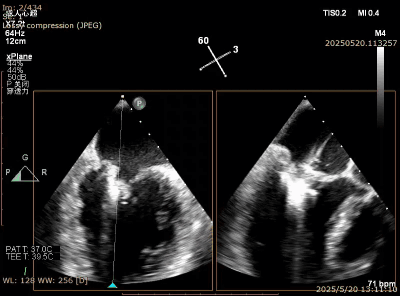

在经股静脉途径的TEER手术时,房间隔穿刺是一个很重要的基础步骤。有时候房间隔组织较韧较厚(多见于房间隔短穿刺位置需要靠后,或者外科房间隔修补术后),穿刺针通过之后要通过导引大鞘(GC)存在着较大困难,若强行推送大鞘可引起房间隔撕裂到左心房顶引起灾难性心包填塞。传统做法时使用外周球囊对房间隔进行扩张,但是不是每个导管室都常规配备外周球囊,且使用过大球囊仍可引起房间隔撕裂风险。我们提供了一种更简洁的方式,即使用导引鞘内芯和房间隔穿刺鞘两个管子(双管齐下)同时扩张房间隔穿刺口,再推送导引大鞘通过房间隔,无需额外器械,操作简单高效且安全(图1-4)。

图4. 顺利送入导引鞘通过房间隔